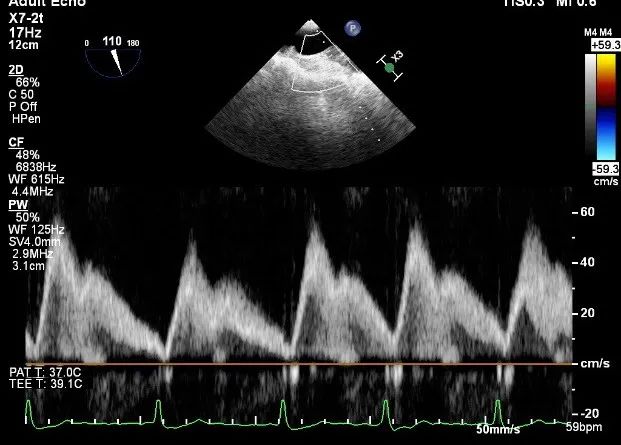

肺静脉血流频谱呈收缩期反向

TEE LVOT切面返流量评估

TEE 4-Ch view返流量评估